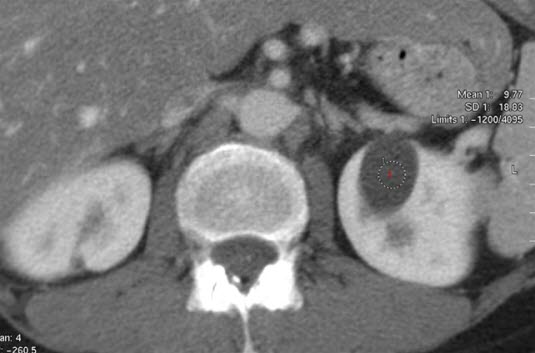

CT axialbilde med i.v. kontrast

Velavgrenset, homogent, lavattenuerende (mørkt) område (1) foran i høyre nyre